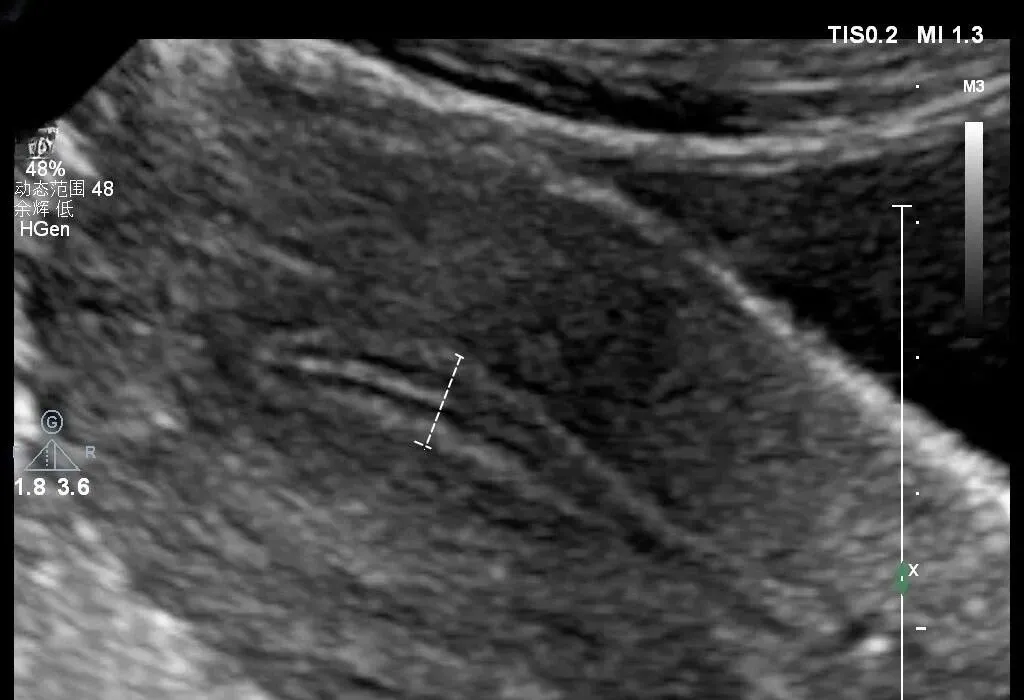

超声正常值的测量

●子宫前后径的测量

★ 测量标准切面:于子宫长径测量切面测量,即子宫正中矢状切面

★ 测量方法:测量与子宫(宫体)长径相垂直的最大前后距离